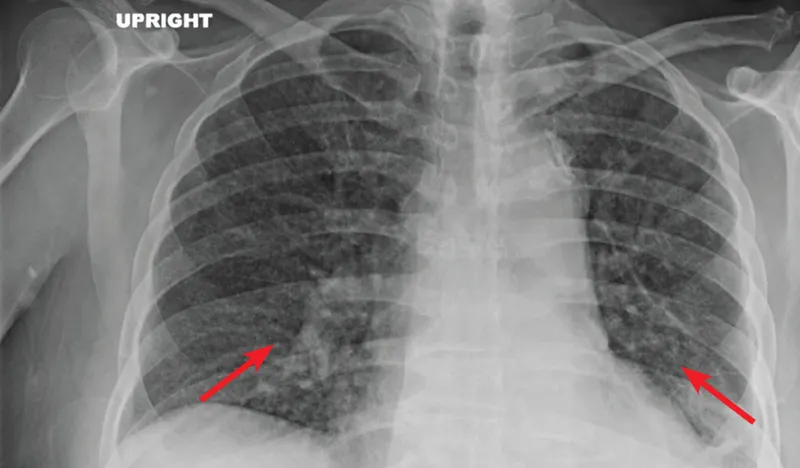

- Clinical presentation is stratified by CD4 count:

- CD4 >200 cells/μL: Classic upper-lobe cavitary pulmonary TB.

- CD4 <200 cells/μL: Atypical patterns; extrapulmonary disease (lymphadenitis, meningitis) and disseminated/miliary TB are common. Chest X-rays can be normal.